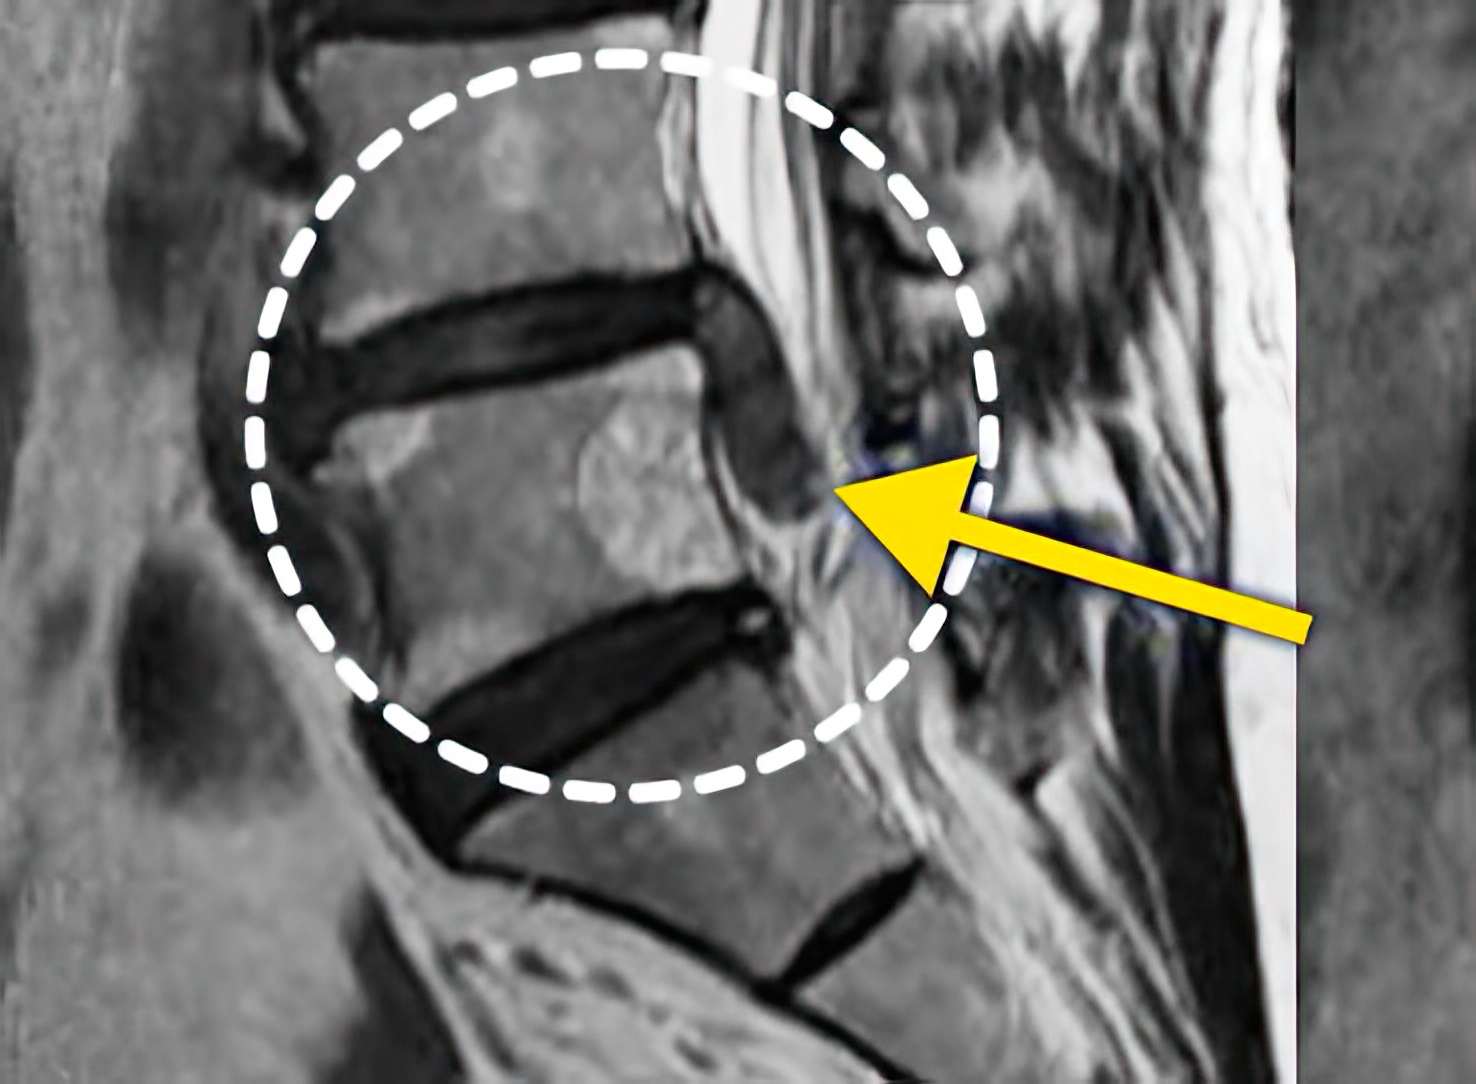

자생 비수술 한방통합치료 후

터진디스크가 흡수된 모습

비수술 치료만으로

터진 디스크 흡수

튀어나온 디스크 대비,

터진 디스크 치료 효과 우수

디스크 흘러내린 정도가

심할수록 흡수 가능성 증가